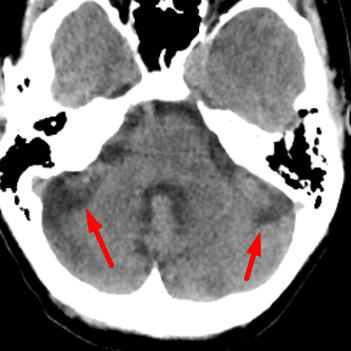

Cerebellar Horizontal Fissure

Case 8